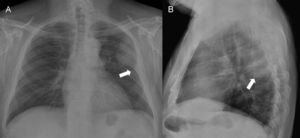

Hallazgos radiológicosEn la radiografía de tórax (fig. 1) se aprecia una opacidad periférica en la región posterosuperior del hemitórax izquierdo con bordes parcialmente bien definidos y de semiología extraparenquimatosa. No hay signos de destrucción costal.

La radiografía torácica muestra una lesión única, periférica y de base amplia, con bordes parcialmente bien definidos y ángulos obtusos con la pared torácica en la proyección posteroanterior (fig. 1A), y bordes mal definidos en la proyección lateral (fig. 1B). Los hallazgos no son definitivos para determinar su origen intra o extrapulmonar y, por tanto, puede tratarse de una lesión de origen pleural (derrame encapsulado, metástasis, mesotelioma y tumor fibroso localizado de la pleura), de pared torácica (lipoma/liposarcoma, histiocitoma fibroso maligno, osteosarcoma, condrosarcoma, metástasis) o pulmonar de asiento pleural (carcinoma primario).